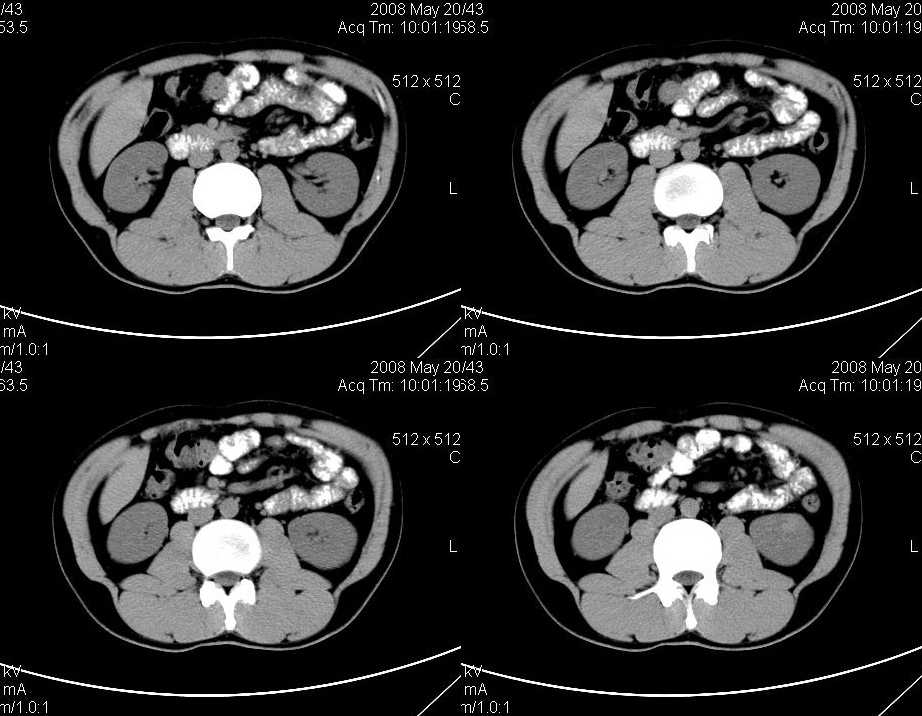

以下是引用liuyue在2008-6-7 15:28:00的发言:[br]典型的:肾癌。[br]动脉期强化明显,而静脉期密度明显降低,呈低密度。